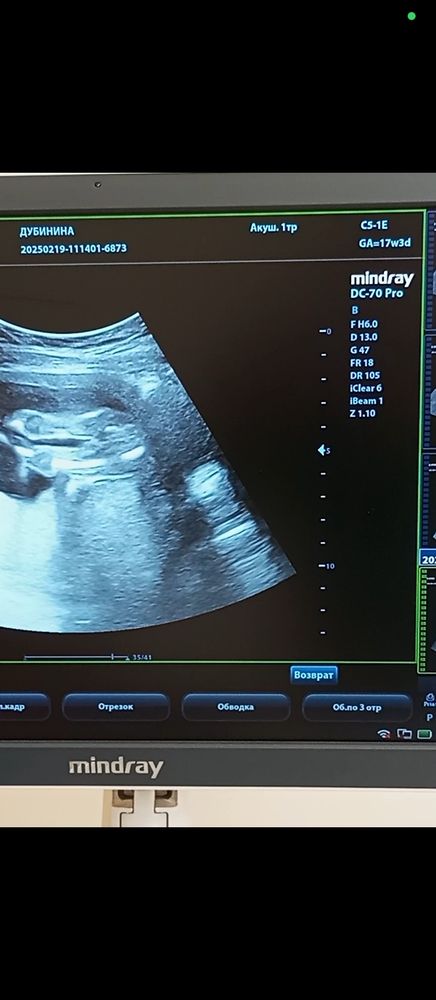

Мальчик. Между ножек хорошо видно)

Как будто бы мальчик.

Больше похоже на мальчика, если это не пуповина конечно между ног так видна

Узи 14 недель♥️ Первое узи♥️знакомство.🥰гематома🥺